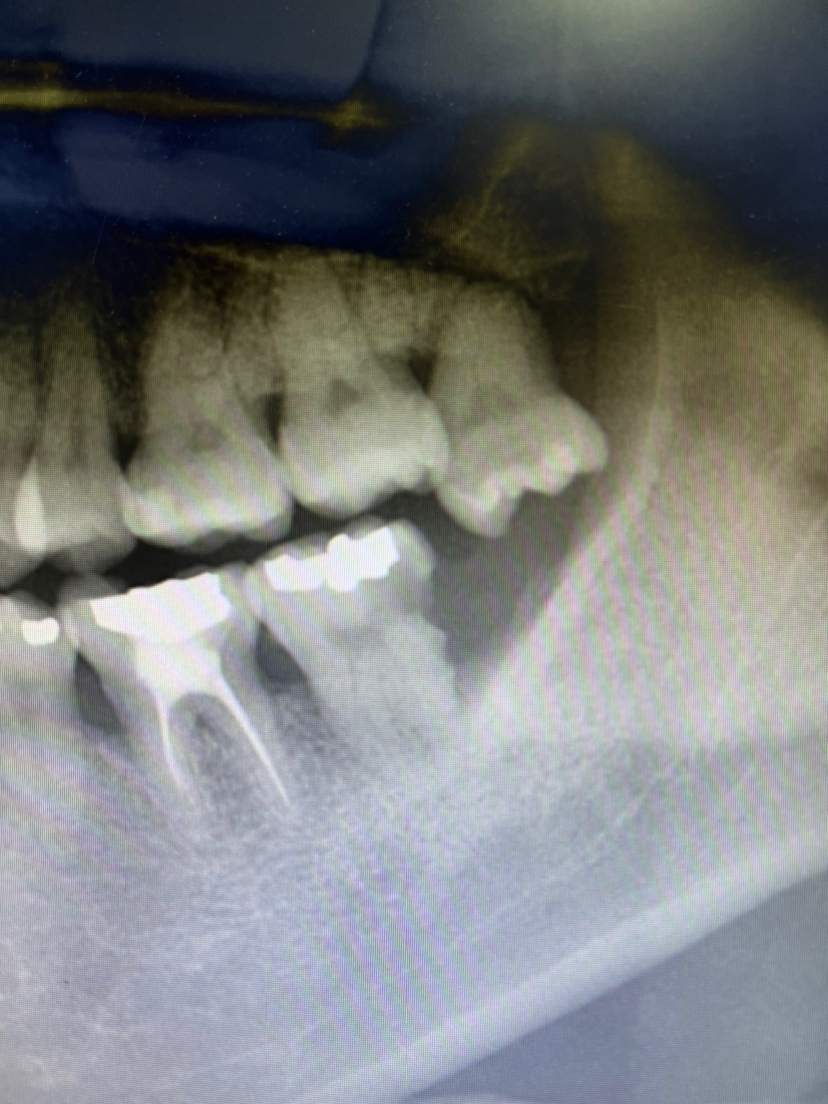

许多口腔疾病在早期并不会引发明显的疼痛感。例如,龋齿和牙周病都可能在初期阶段毫无症状。这使得很多人错误地认为自己的牙齿健康。实际上,即便牙齿没有任何不适,内部仍然可能隐藏着许多潜在问题。

1.龋齿:早期龋齿可能不会导致疼痛,但随着时间的推移,它会逐渐侵蚀牙齿,甚至影响到牙髓,导致严重的疼痛。

2.牙周炎:这种疾病通常从无痛的牙龈炎开始,如果不加以重视,可能发展为更严重的牙周炎,导致牙齿松动或脱落。

3.牙髓炎:在某些情况下,牙髓炎可能在早期没有疼痛感,随着感染的发展,最终会导致剧烈的疼痛和其他并发症。

- 龋齿:最初的白斑或小洞可能不伴随疼痛,但如果不及时治疗,可能导致深层龋齿,引发疼痛。

- 牙周炎:早期的牙龈出血、红肿等症状往往被忽视,患者可能感觉正常,然而这些都是牙周炎的警示信号。

- 牙髓炎:此病可能在感染初期不出现疼痛,但随着病情加重,最终会导致强烈的疼痛反应,需要紧急处理。